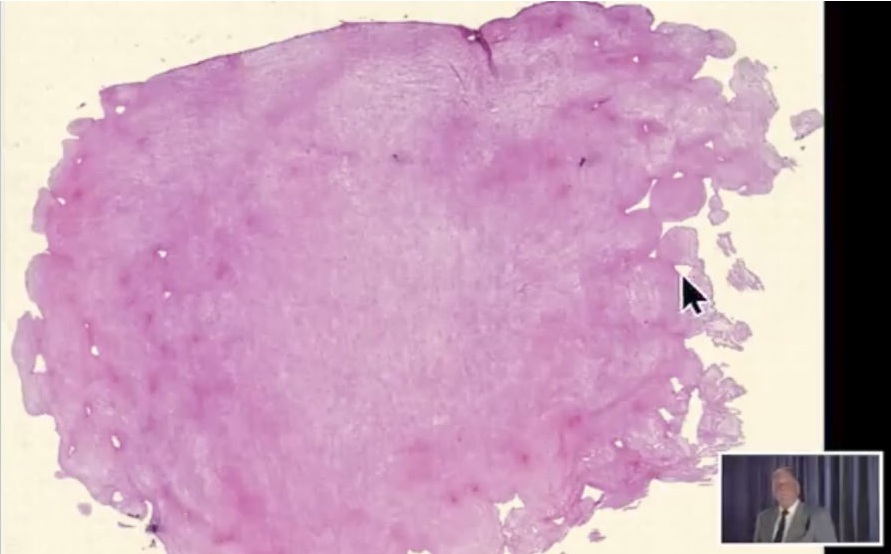

Video 9.10.2021: Pfizer

vaccine=toxic agent! -

Pfizer-Impfstoff=Kampfstoff! Objekte+Fäden

(25''): https://www.bitchute.com/video/YqnKldt4iyOH/

Pfizer-Impfstoff=Kampfstoff! (25'')

Link: https://www.bitchute.com/video/YqnKldt4iyOH/

- Bitchute-Kanal: NatMed-etc. - hochgeladen am

10.10.2021